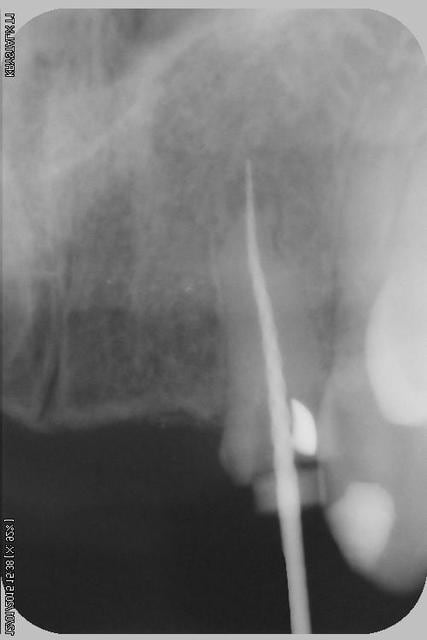

le scan n'est pas terrible, mais suffisant pour voir que 22 une fois extraite, ne va pas etre simple à implanter, par contre 11/21 avec un peu d'expansion...

Donc dans un premier temps,je décide d'essayer de retraiter 12/22, de toute façons ça ne peut pas être pire que ce qui tiens depuis 10 ans... enfin 12 mobilité quasiment 3.

Sur la reprise de 22 je pense que tu as fais un beau "tout-droit" à l'apex... le canal devait suivre la courbure.

Tu es bon pour faire une chir-apicale dans quelques mois !

je pense que le tout droit existait déjà..

Oui oui, c'est certain ! il y avait au moins une belle butée bien engagée. Ce qui expliquerai que l'ancien traitement n'allait pas jusqu'à l'apex.

Et avec les instruments de rotation continue agressifs de reprise d'endo que l'on a maintenant, on s'engage dans la butée et on la "termine"... ça m'arrive aussi de temps en temps... de toutes façons, repasser de vieilles butées comme ça, même les endos exclusifs n'y arrivent presque jamais et font une chir apicale d'emblée.